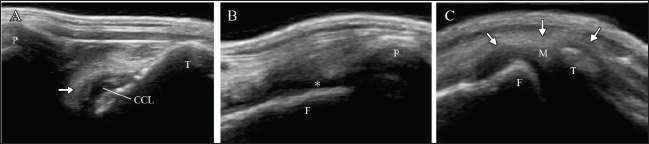

Radiography of the right stifle joint indicated infrapatellar fat pad signs and cranial tibial luxation (Fig. 1A). No obvious angular limb deformities were observed (Fig. 1A and D). Ultrasonography of the stifle joints (ARIETTA Prologue; Fujifilm Co., Japan; 18 MHz linear probe) revealed a complete CCLR, severe joint effusion, and medial buttress in the right stifle joint with no injury to the medial meniscus (Fig. 2A–C). Furthermore, partial CCLR and mild joint effusion were observed in the left stifle joint.

Fig. 2. Ultrasonography of the right stifle joint at the first visit. Complete rupture of the cranial cruciate ligament (arrow, A) and severe joint effusion (asterisk, B) can be observed. Although the medial buttress (arrow, C) can be visualized, the caudal horn of medial meniscus shows no damages (C). CCL=cranial cruciate ligament; F=femur; M=medial meniscus; P=patella; T=tibia.

Fig. 5. Ultrasonography of the left stifle joint at 8 weeks after surgery on the right limb. The joint shows complete rupture of cranial cruciate ligament (arrow, A), moderate joint effusion (asterisk, B), and the medial buttress (arrow, C). The caudal horn of medial meniscus shows no injury (C). CCL=cranial cruciate ligament; F=femur; M=medial meniscus; P=patella, T=tibia.